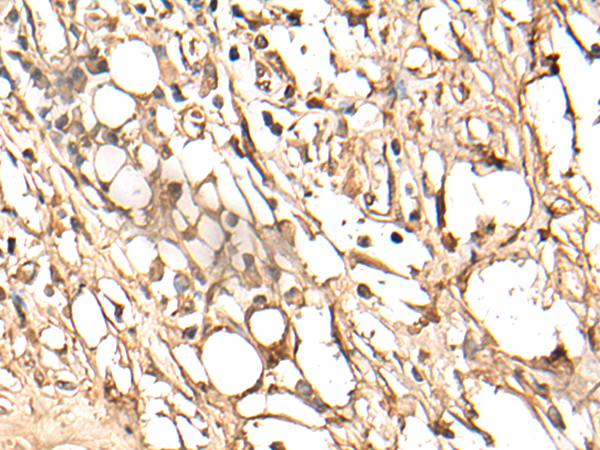

IHC positive control: |

Human gastric cancer |

IHC Recommend dilution: |

25-100 |